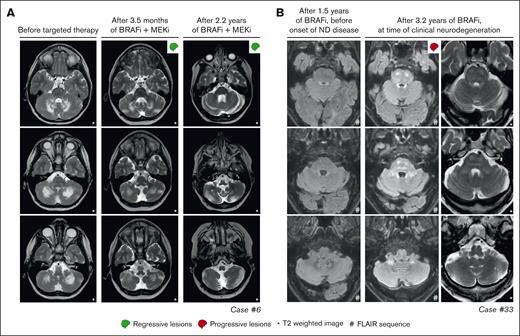

In 4 of 27 patients with multisystemic and/or solid lesions, brain lesions characteristic of histiocytosis-associated neurodegeneration were present on MRI at targeted therapy initiation. Only 1 of 4 also had clear neurologic symptoms (patient 32 with dysarthria). During targeted therapy, radiologic response of the brain lesions was noted in case 17 (supplemental Figure 1A), whereas lesions remained stable in 2 of 4 and were not evaluated in case 32, who appeared to have a slight improvement in dysarthria. One of the patients with stable brain lesions during targeted therapy (patient 14 with ECD) had progressive radiologic abnormalities in the pons and cerebellum at 4 and 7 months after stopping vemurafenib because of toxicity (supplemental Figure 1B). This patient did not have progressive neurologic symptoms; therefore, no treatment was initiated. At 2 years after stopping vemurafenib, the patient’s clinical and radiologic situation remained stable. Another patient (case 33 with LCH/ECD) developed new radiologic abnormalities in the pons and cerebellum and clinical symptoms of neurodegeneration after almost 3 years of treatment with vemurafenib (Figure 5B). The patient subsequently received (methyl)prednisolone and increased doses of vemurafenib (up to twice daily 720 mg; 4 out of 6 days), without a clinical response. Eventually, targeted treatment was switched to dabrafenib, but the patient requested euthanasia a few weeks later and died shortly thereafter.

Response and progression of ND lesions. (A) Axial MRI images of case 6, with isolated ND-LCH showing significant reduction in T2-hyperintense lesions after treatment with dabrafenib and trametinib. Note that the remaining hyperintense lesion in the right cerebellum at last follow-up (right column; middle image) is related to the biopsy that was taken from this anatomical site. (B) Axial MRI images of case 33 showing the development of T2- and FLAIR-hyperintense lesions in the pons and cerebellum while receiving treatment with vemurafenib. The patient also developed clinical symptoms of neurodegeneration and died 7.5 months after the MRI scan depicting ND lesions was made. ND, neurodegenerative; FLAIR, fluid-attenuated inversion recovery.

Among the 8 patients receiving targeted therapy for ND-LCH, 2 had a PR of radiologic abnormalities (Figure 5A), 4 had stable lesions, and 2 stopped therapy before response could be evaluated (Figure 2). The 2 patients with a response were treated within 2 years after diagnosis of LCH, whereas the 4 with stable lesions started targeted therapy between 5 and 20 years after diagnosis of LCH. The radiologic response was accompanied by improvement of cognitive symptoms of memory impairment and concentration difficulties in case 10 (who did not have ataxia/dysarthria), whereas repeated neurologic assessments in case 6 showed a rather stable situation, with only slightly improved International Cooperative Ataxia Rating Scale scores (45 to 42).62